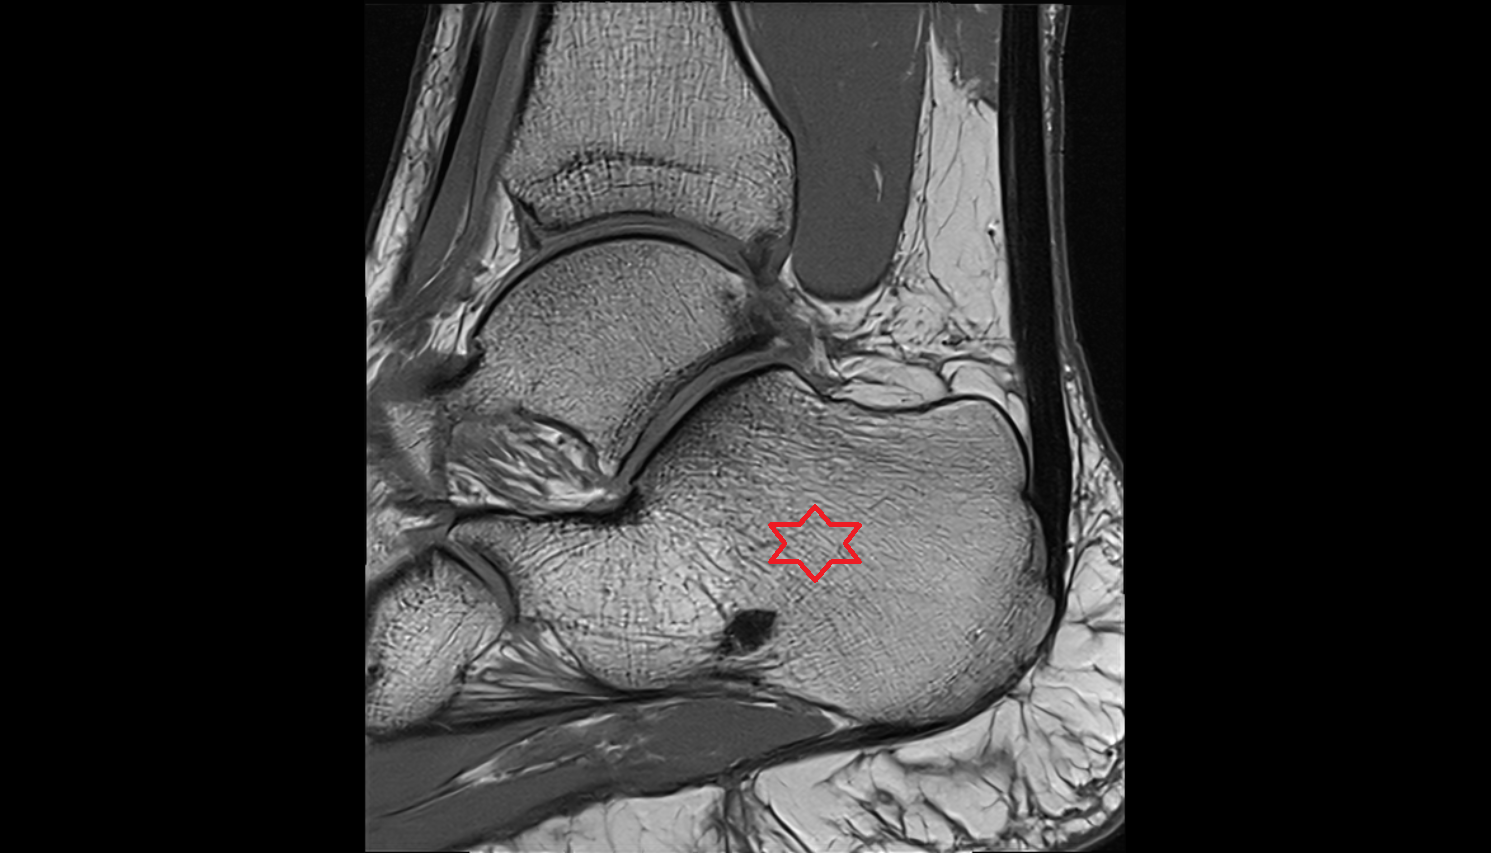

- Calcaneus